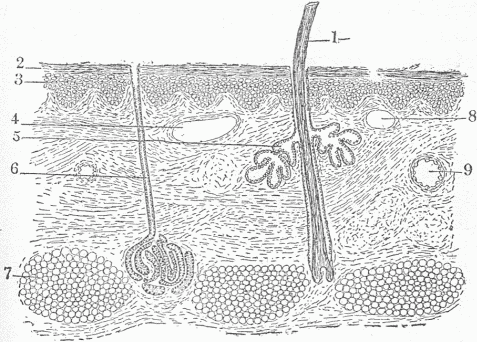

Fig. 3.—A Section Of The Skin. 1. A hair. Notice there is a deep depression of the surface to form a small bulb from which the hair grows. 2. The superficial or horny layer of the skin; the cells here are joined to form a dense, smooth, compact layer impervious to moisture. 3. The lower layer of cells. In this layer new cells are continually being formed to supply those which as thin scales are cast off from the surface. 4. Section of a small vein. 9. Section of an artery. 8. Section of a lymphatic. The magnification is too low to show the smaller blood vessels. 5. One of the glands alongside of the hair which furnishes an oily secretion. 6. A sweat gland. 7. The fat of the skin. Notice that hair, hair glands and sweat glands are continuous with the surface and represent a downward extension of this. All the tissue below 2 and 3 is the corium from which leather is made.

All of the causes of disease act on the body from without, and it is important to understand the relations which the body of a highly developed organism such as man has with the world external to him. This relation is effected by means of the various surfaces of the body. On the outside is the skin [Fig. 3], which surface is many times increased by the existence of glands and such appendages to the skin as the hair and nails. A gland, however complicated its structure, is nothing more than an extension of the surface into the tissue beneath [Fig. 4]. In the course of embryonic development all glands are formed by an ingrowth of the surface. The cells which line the gland surface undergo a differentiation in structure which enables them to perform certain definite functions, to take up substances from the same source of supply and transform them. The largest gland on the external surface of the body is the mammary gland [Fig. 5] in which milk is produced; there are two million small, tubular glands, the sweat glands, which produce a watery fluid which serves the purpose of cooling the body by evaporation; there are glands at the openings of the hairs which produce a fatty secretion which lubricates the hair and prevents drying, and many others.